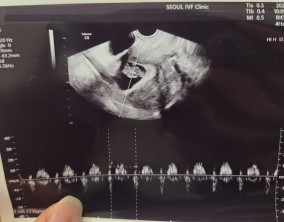

이유정 원장님은 매 순간 환자의 마음을 읽어주시는 분이었어요. 부담 없이, 그러나 가장 효과적인 방향으로 치료를 이끌어주셨고, 그 덕분에 PGT-A에서 무려 5개의 통과 배아를 얻…